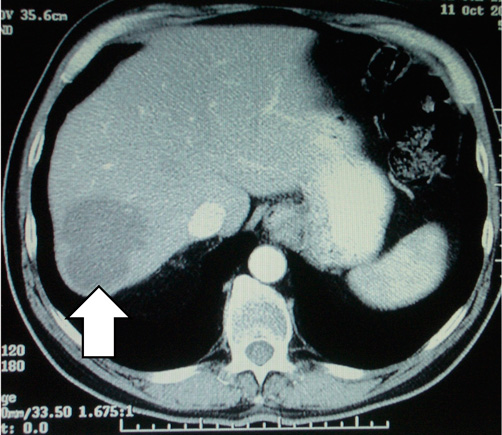

These CT scans show a secondary deposit in the liver from a cancer of the colon, before chemotherapy (left) and after chemotherapy (right). The patient then underwent surgery, but the significant shrinkage made for a lesser operation.